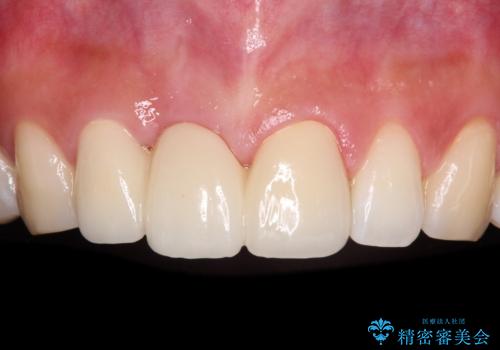

折れているのに応急処置でごまかしてきた前歯 オールセラミックブリッジによる補綴治療

抜歯による歯槽骨や歯肉が陥没して審美障害を起こすことがありますが、今回は仮歯でも違和感のない外観となったため、歯肉移植術を行うことなく仕上げることができました。